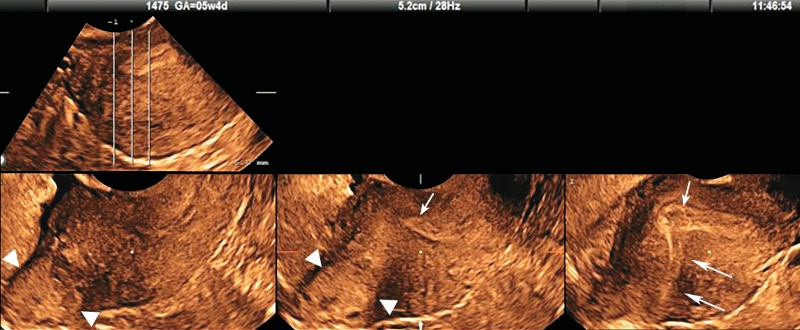

етрия на узи

Утолщения эндометрия на узи 113 фотографий